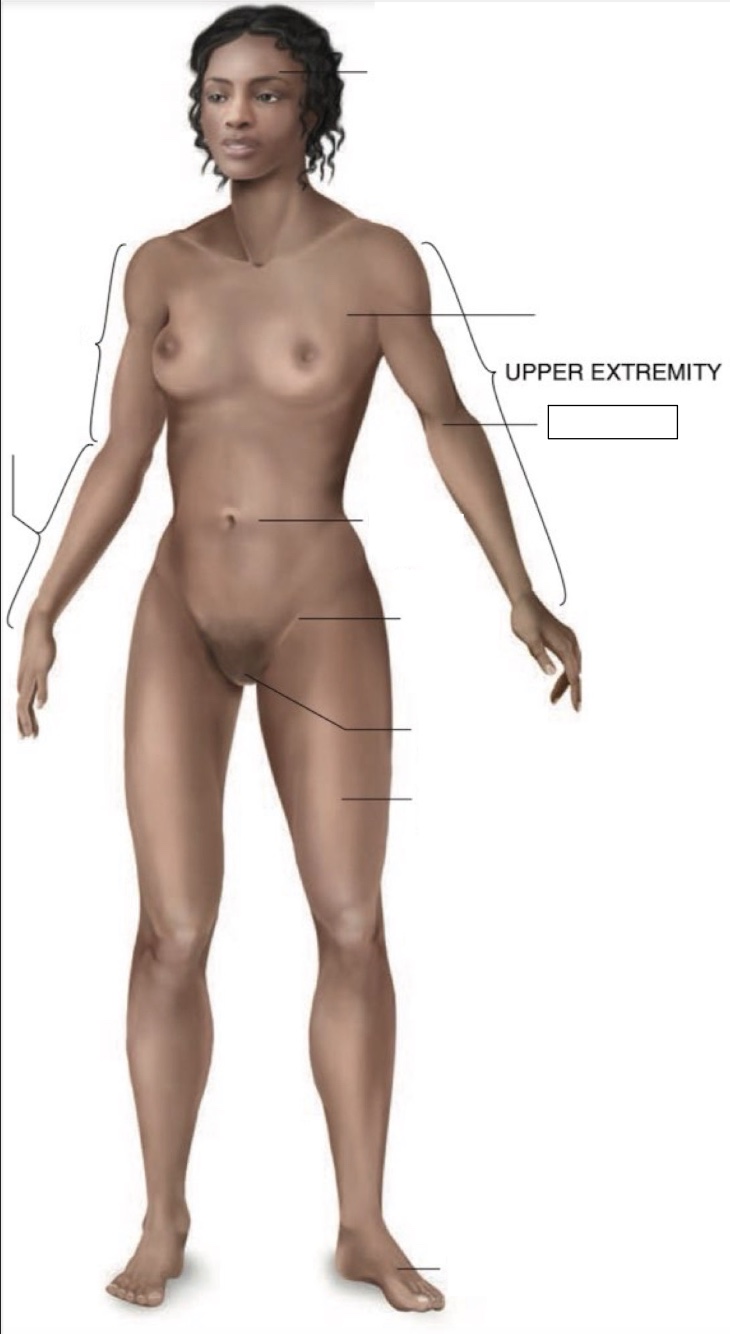

Cranial region

thoracic region

umbilical region

inguinal region

genital region

femoral region

dorsum of foot

arm

forearm

cubital region

Torso

Inferior

Midline